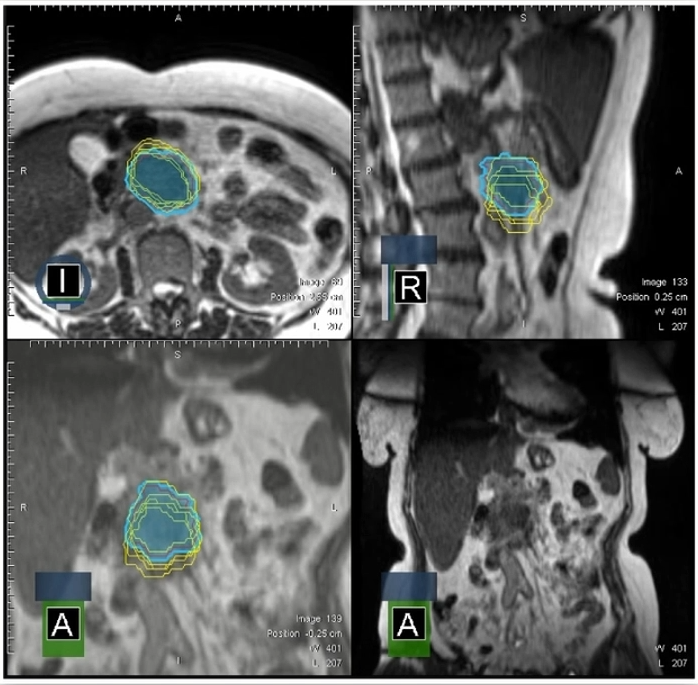

在出束中进行患者端自反馈系统的实时软组织追踪和自动出束门控

在放疗期间,患者体内可能会因为呼吸运动、胃肠内气体变化等,导致肿瘤和周围危及器官(OARs)的位置和形状迅速改变。MRIdian可以采集磁共振电影成像(8帧/秒)并自动追踪靶组织和危及器官,当肿瘤(例如图11右下红色勾画)移动到预设的治疗窗(例如图11右下黄色勾画)之外或是危及器官移动到治疗窗之内,设备自动停束;当肿瘤移回治疗窗之内,设备自动恢复出束。同时在治疗过程中,患者也能看到这些实时MRI电影成像,因而可以自主反馈地控制呼吸,使得其体内肿瘤在尽量多的时间内进入治疗窗,这大大增加了患者在治疗肿瘤时的信心,同时提高了治疗效率。

图 11 MRIdian的实时电影成像(8帧/秒)和患者端自反馈的组织追踪和自动门控